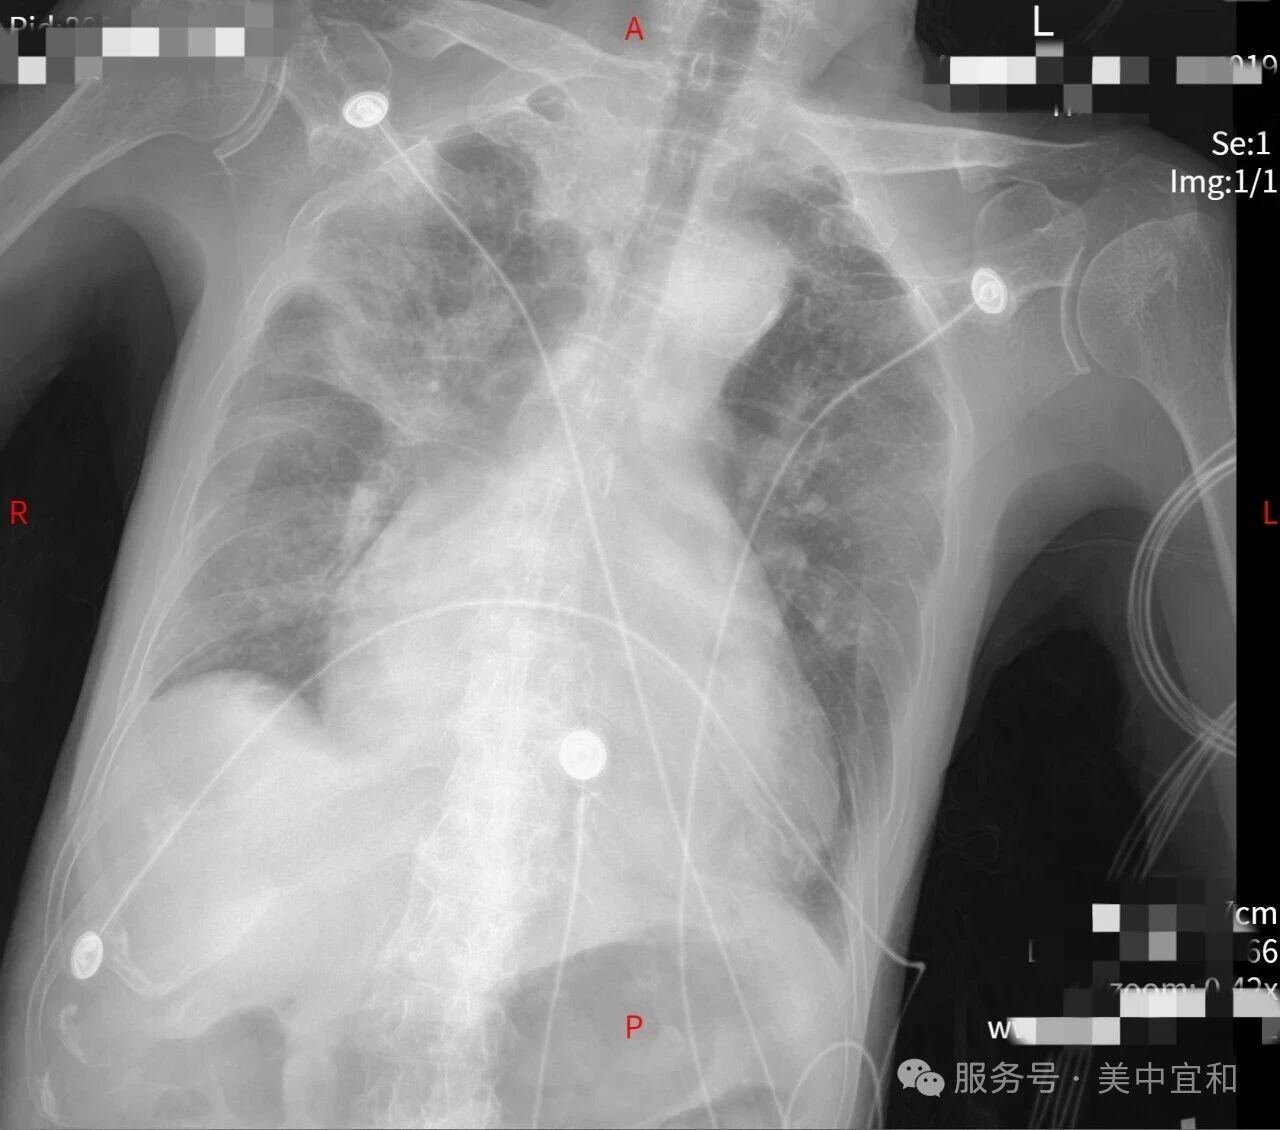

老先生来到呼吸科就诊时,咳嗽、咳痰、喘息的症状已经加重 4 天了,并且出现咳粉红色泡沫痰的症状,结合外院检查,呼吸科李主任初步判断患者为「重症肺炎合并心力衰竭」,患者高龄,基础疾病较多,既往还有房颤病史,此次入院 3 个月前刚发生脑梗塞,但目前凝血功能异常,救治上需要兼顾抗凝与出血的风险,据文献报道,此类患者死亡率显著升高,可达 50%-70%[1]。李主任果断地将患者收治入院,一场多学科合作下的生命接力赛立即展开。

检查结果患者 BNP 高达 5595pg/mL(正常<100pg/mL),提示重度心功能不全(BNP>1000pg/mL 即属于高死亡风险)。同时合并房颤,心脏泵血功能显著下降。

血气分析提示患者低氧血症+代谢性酸中毒,肺部感染 CRP 显著升高加重肺循环阻力,他的呼吸功能已明显受损。而炎症因子(病毒、细菌、真菌混合)也会损伤心肌细胞,双重加重心衰。